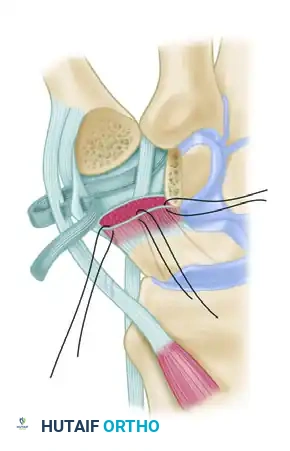

Figure: Schema of ligament support. The key volar ligament is a reflection of the transverse carpal ligament after insertion into the crest of the trapezium. Note the FCR passing directly beneath this ligament.

Figure: A 6- to 8-cm strip, representing half the width of the FCR tendon, is split away while remaining in continuity distally.

Figure: Path of the FCR strip rerouted to enter the volar channel at the beak of the metacarpal.

Figure: Schema of volar and radial ligament reconstruction. The complex course of the tendon strip creates robust reinforcement in the volar, dorsal, and radial aspects of the joint.

Figure B: FCR tendon passed through the bone tunnel while the index and thumb metacarpal bases are approximated.

*Figure C: FCR tendon passed between